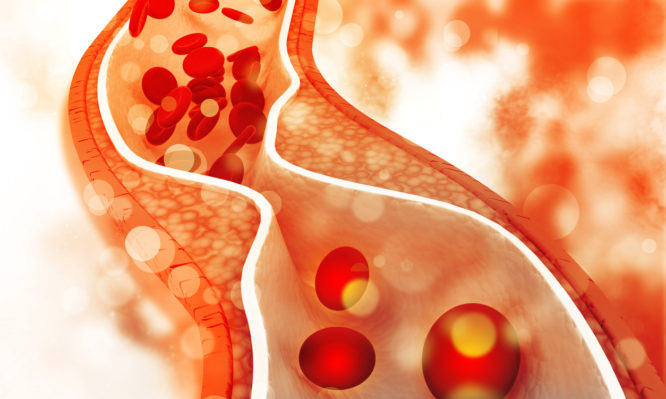

Όλοι οφείλουμε να προσέχουμε τα επίπεδα που έχει η χοληστερίνη στο αίμα μας. Σε κάθε περίπτωση, οι ακόλουθες τροφές είναι πιο ασφαλείς και λιγότερο πιθανό να αυξήσουν την χοληστερίνη σας. Μην ξεχνάτε, ωστόσο, ότι τα πάντα στην διατροφή είναι θέμα μέτρου και ποικιλίας.